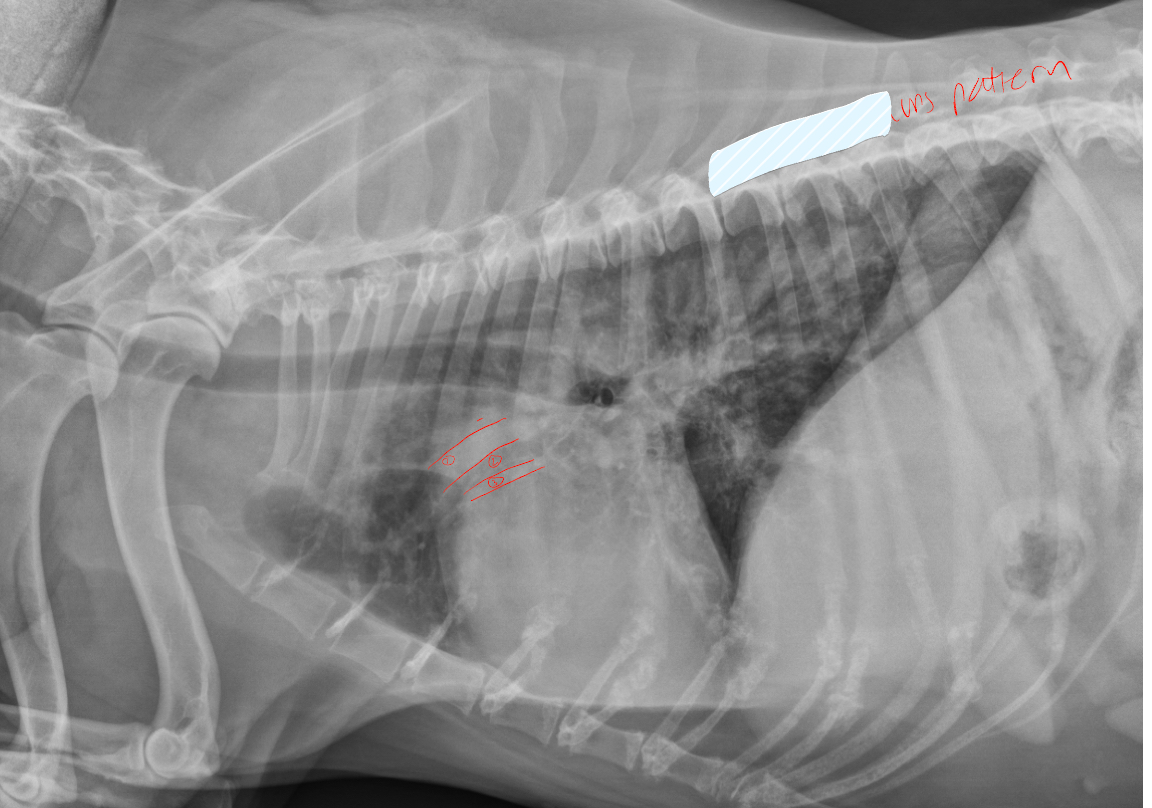

taken from 5yr old dog, identify 1+ 3, lung pattern and what is likely dx

A

1. Pulmonary artery (enlarged)

2. Pulmonary vein

Lung pattern: interstitial

Dx: heartworm disease